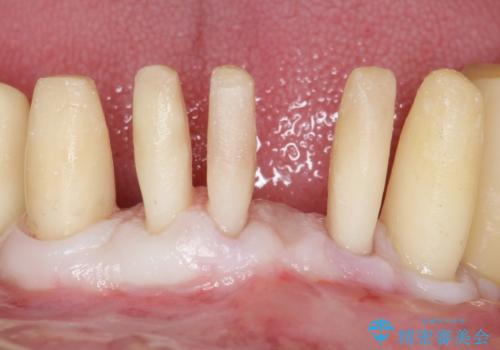

歯も神経も残したいという患者様のご希望により、補綴前に部分矯正を行っております。

補綴前に部分矯正を行うことで、歯の神経も保存することができました。

生活歯(神経が生きている歯)のため形成量(歯を削合できる量)に限界がありましたが、熟練の技工士さんの素晴らしい技術により補綴を行うことができました。